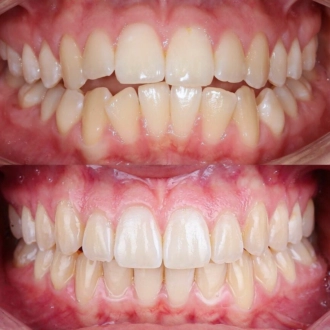

Комплексная гигиена зубов: гигиеническая чистка скейлером + аппаратом Air-Flow + полировка зубов профессиональной пастой